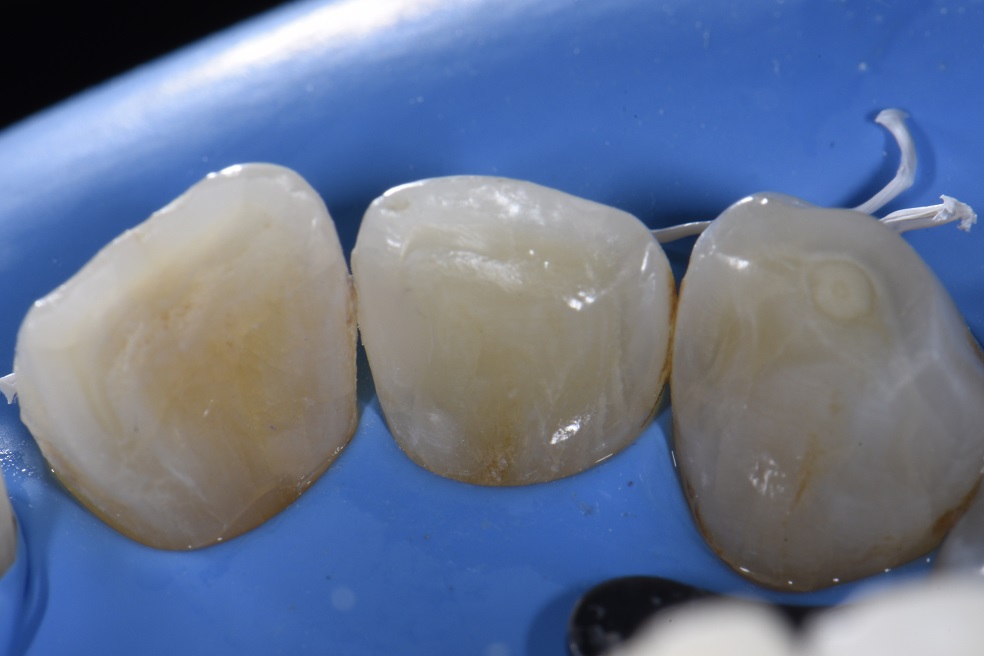

Dental Class 3 Restoration . Preparation outline is determined by the extent of the carious lesion, defects, or old restorative material. It is generally formed with. this paper aims to provide the dentist with practical guidance on the technique for direct composite restoration. dental restoration ranges in price, dependent on what type of restoration you require and which dental clinic you are visiting. in general, the tooth preparation for a class iii direct composite restoration involves (1) obtaining access to the defect (caries,. at first glance, a class iii direct composite restoration can appear to be a fairly routine procedure.